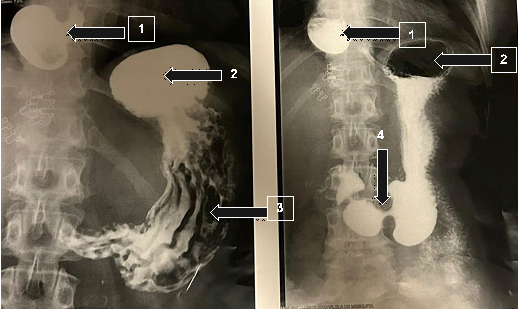

An upper digestive endoscopy was carried out one month after the first consultation, in which the presence of a diverticulum 35 cm from the incisors (in the lower third), with food content, was observed in the esophagus. The mucosa was unchanged and the vascular pattern was preserved. In addition, the esophago gastric transition, located 40 cm from the incisors, coincided with diaphragmatic clamping and was within normal limits. The results for the stomach showed a normal shape, volume and distensibility of the organ. There was also a small amount of hyaline stasis fluid in the usual colour. The mucosal fold and antral peristalsis were preserved. The retro vision manoeuvre showed the hiatus adjusted in relation to the endoscope and visualized some flat erosions in the gastric antrum mucosa, with a centered and patent pylorus. In the duodenum, the bulb had a preserved lumen and mucosa, and the second portion had intact folds and mucosa. A biopsy of the gastric mucosa was also taken for urease testing, with negative results for Helicobacter pylori. Diagnostic impression: esophageal diverticulum with food content at 35 cm from the incisors and mild erosive antral gastritis (Figure 1). Esophageal manometry, a test that assesses the pressure tone and motility of the esophagus, was carried out 2 months after the first visit and showed the upper esophageal sphincter situated 17 to 20 cm from the nostril with an extension of 3 cm, a mean respiratory pressure at rest of 35.3 mmHg and normal relaxation. The body of the esophagus showed asynchronous peristalsis. The average amplitude was 10 wet swallows at 03 cm above the IES of 81.7 mmHg. The lower esophageal sphincter, located between 39.5 and 45.5 cm from the nostril, was 6.0 cm long, with a PIP of 42.5 cm from the nostril, and was predominantly intra-abdominal. In addition, mean respiratory pressure (MRP) at rest was 33.5 mmHg and relaxation was normal.

Figure 1 Upper digestive endoscopy findings. Arrow (1) Esophageal lumen, Arrow (2) epiphrenic diverticulum in the esophageal lumen.